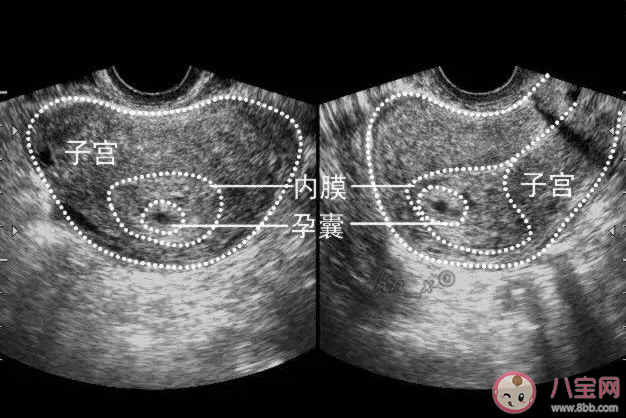

空囊是指孕妇在怀孕一段时间后,B超检查孕囊中没有卵黄囊、胚芽、胚心。是胚胎停止发育的一种类型。

空孕囊主要表现为阴道流血,血hcg翻倍不好,孕酮较低,经过保胎治疗后,胚胎不能继续发育下去。但临床症状因人而异,也有无症状的,主要通过超声检查来发现。大多怀孕后第七周时超声检查不见卵黄囊、不见胚芽、不见胎心,就基本可以确定。

一般怀孕8周左右会出现胎芽,怀孕8周后仍然没有发现胎心,可能是空孕囊。所以怀孕8周是做B超的最佳时期,能及时了解胚胎和胎盘发育情况。